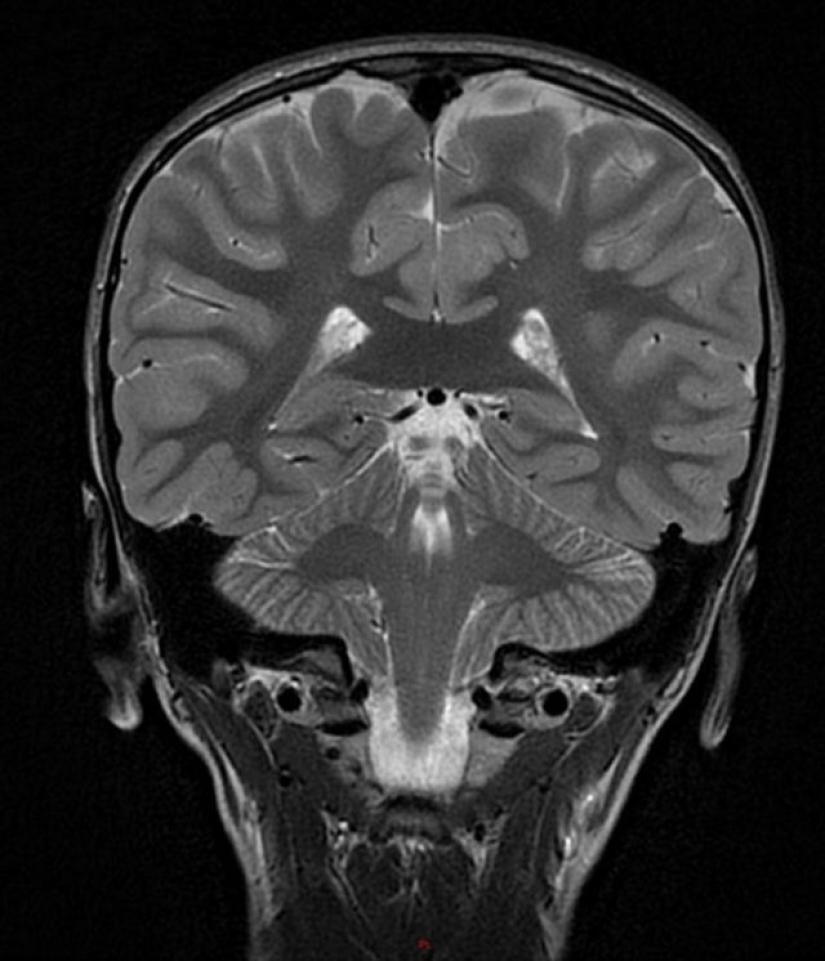

2. “Aparentemente, hay un niño pequeño en el cerebro de mi hijo. Y no es photoshop.